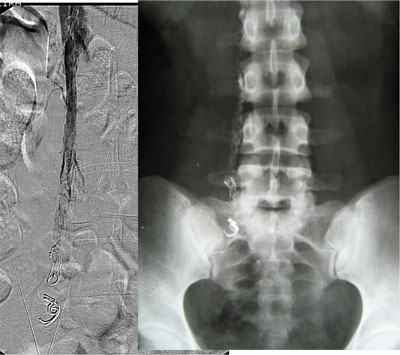

Paciente de 32 anos, feminino, nulípara, procurou consultório com queixa de fadiga nos membros inferiores e varizes vulvares que desciam até a face posterior da coxa direita. Realizado ultrassonografia com Doppler colorido de membros inferiores que mostrou normalidade das veias safenas e do sistema venoso profundo e identificou que as varizes da coxa direita corriam em direção a região genital. Solicitado ultrassonografia endovaginal com Doppler colorido que mostrou varizes pélvicas, sendo de maior calibre junto aos anexos à direita, com diâmetro máximo de 8 mm. A paciente foi submetida a flebografia que mostrou refluxo da veia ovariana direita com progressão do meio de contraste até a vulva. Realizado embolização da veia ovariana direita distalmente com polidocanol 3% para oclusão das colateriais pélvicas e com molas e histoacryl ao longo do seu tronco principal. A flebografia de controle mostrou oclusão completa da veia ovariana direita. Após 30 dias a paciente foi submetida à cirurgia convencional de varizes de membros inferiores através de mine-incisões da pele. Não houve intercorrências relacionadas ao procedimento endovascular e cirúrgico. No seguimento de 10 meses a paciente encontra-se assintomática e sem novas varizes, apresentando telangectasias residuais.